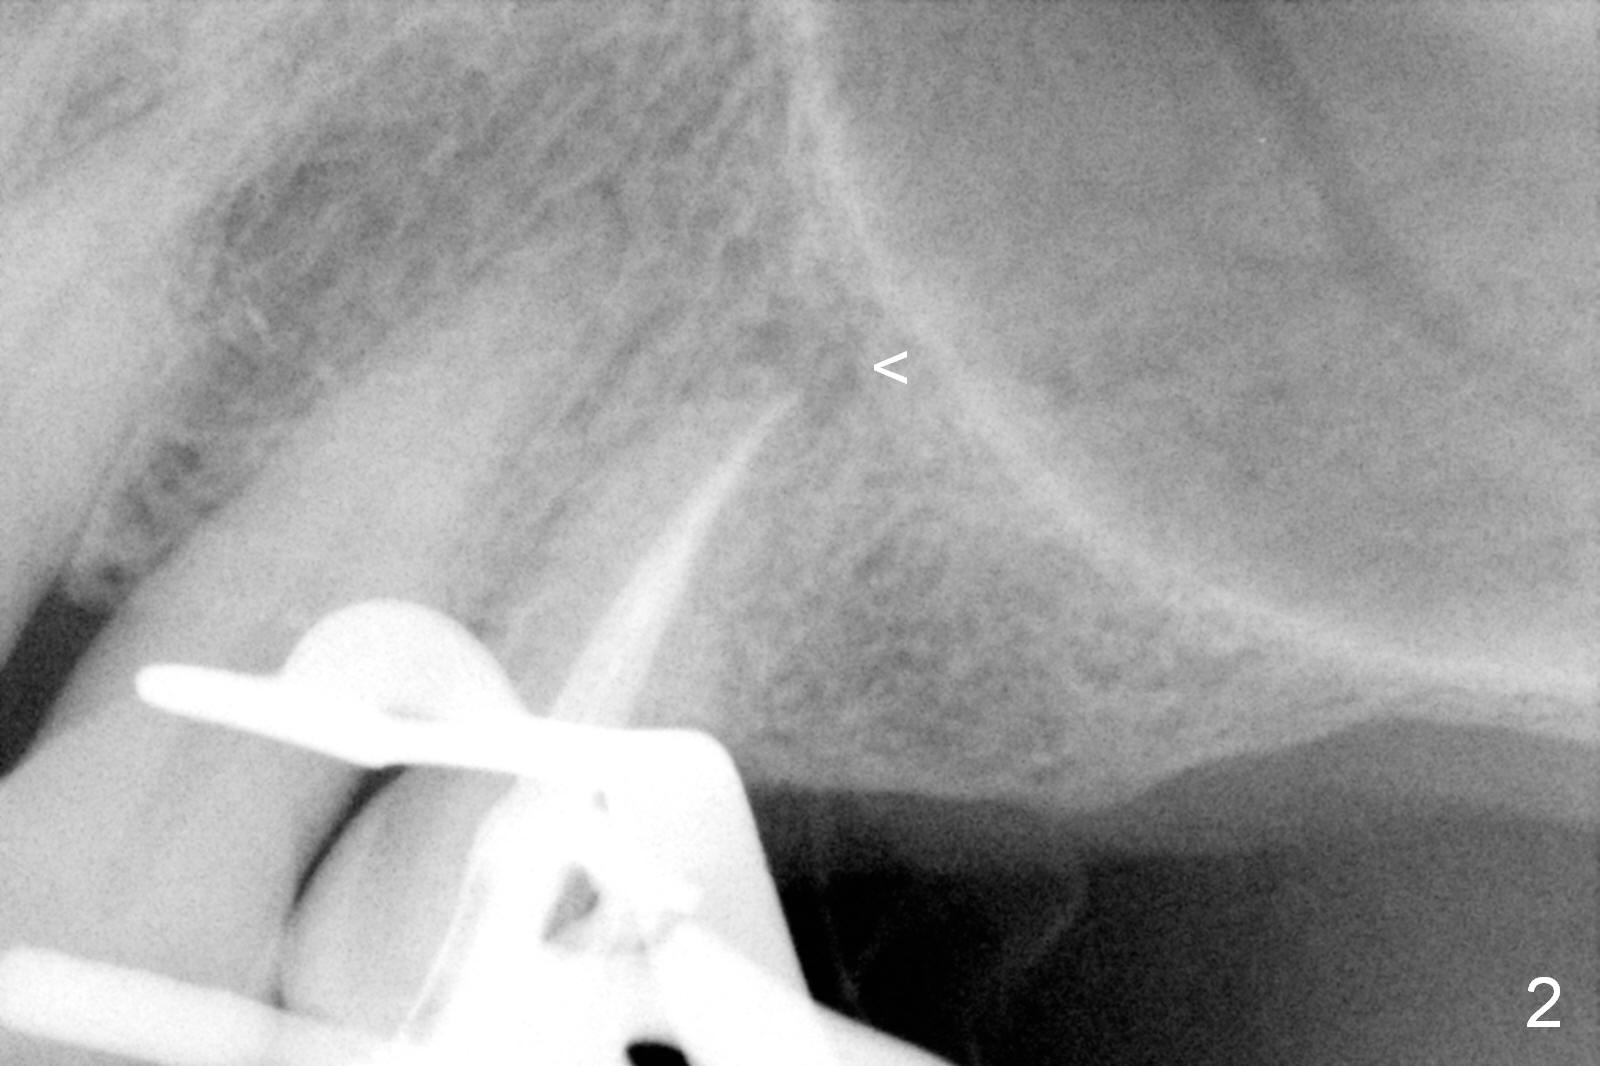

A 64-year-old man (MM) had caries at the tooth #12 (Fig.1), requiring root canal therapy (RCT, Fig.2). One year later, the periapical radiolucency reduces (Fig.3 <, as compared to that in Fig.2). The tooth remains asymptomatic 7 years posts RCT (Fig.4). A year later, the tooth has pain and buccal gingival swelling (probing tenderness); periradicular radiolucency is evident (Fig.5 arrowheads). It appears that the root fractures. Between the 7th and 8th years post RCT, the patient masticated mainly on the left side, while implants were placed at #30 and 31. The patient plans to have 4 implants in the upper left sextant (Fig.6). While implants are being placed at the site of #12 (Clindamycin) and 13, sinus lift seems mandatory at the sites of #13 and (initial depth will be 5-6 mm). By the time implants to be placed at #14 and #15, the bone height may increase.